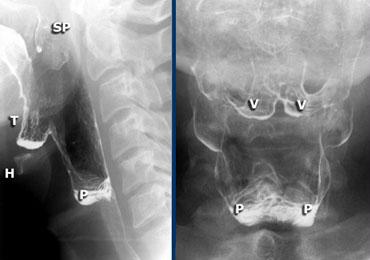

TRÁI: Tư thế nghiêng khi bệnh nhân phát âm “aaa”. Xương móng (H) và nền lưỡi (T) di chuyển ra trước. Xoang hình lê trái và phải được chiếu chồng lên nhau. Đầu mút của màn hầu (SP) được quan sát thấy. PHẢI: Các hố lưỡi-thanh thiệt (V) và xoang hình lê (P).

Hình ảnh đối quang kép của hầu họng

Đối với tư thế nghiêng, yêu cầu bệnh nhân phát âm “aaa”, vì điều này sẽ đưa lưỡi về phía trước và cho phép quan sát tốt hơn vùng hầu miệng và hạ hầu.

Trong tiếng Hà Lan, đây là chữ “eee”, vì được phát âm tương tự như “aaa” trong tiếng Anh.

Đối với tư thế AP, nghiệm pháp Valsalva cải tiến được thực hiện.

Bệnh nhân phải thổi hơi qua môi mím chặt như khi thổi kèn trumpet, đồng thời thư giãn vùng cổ.

Luôn thực hành nghiệm pháp này trước khi thăm khám để bệnh nhân biết cách thực hiện.

Bên trái là hình ảnh đối quang kép của hầu họng.

Sự phồng ra của thành bên hầu họng là bình thường và có thể khá rõ rệt (như trường hợp Dizzy Gillespie).

Những cấu trúc này được gọi là ‘tai hầu bên’ (lateral pharyngeal ears).